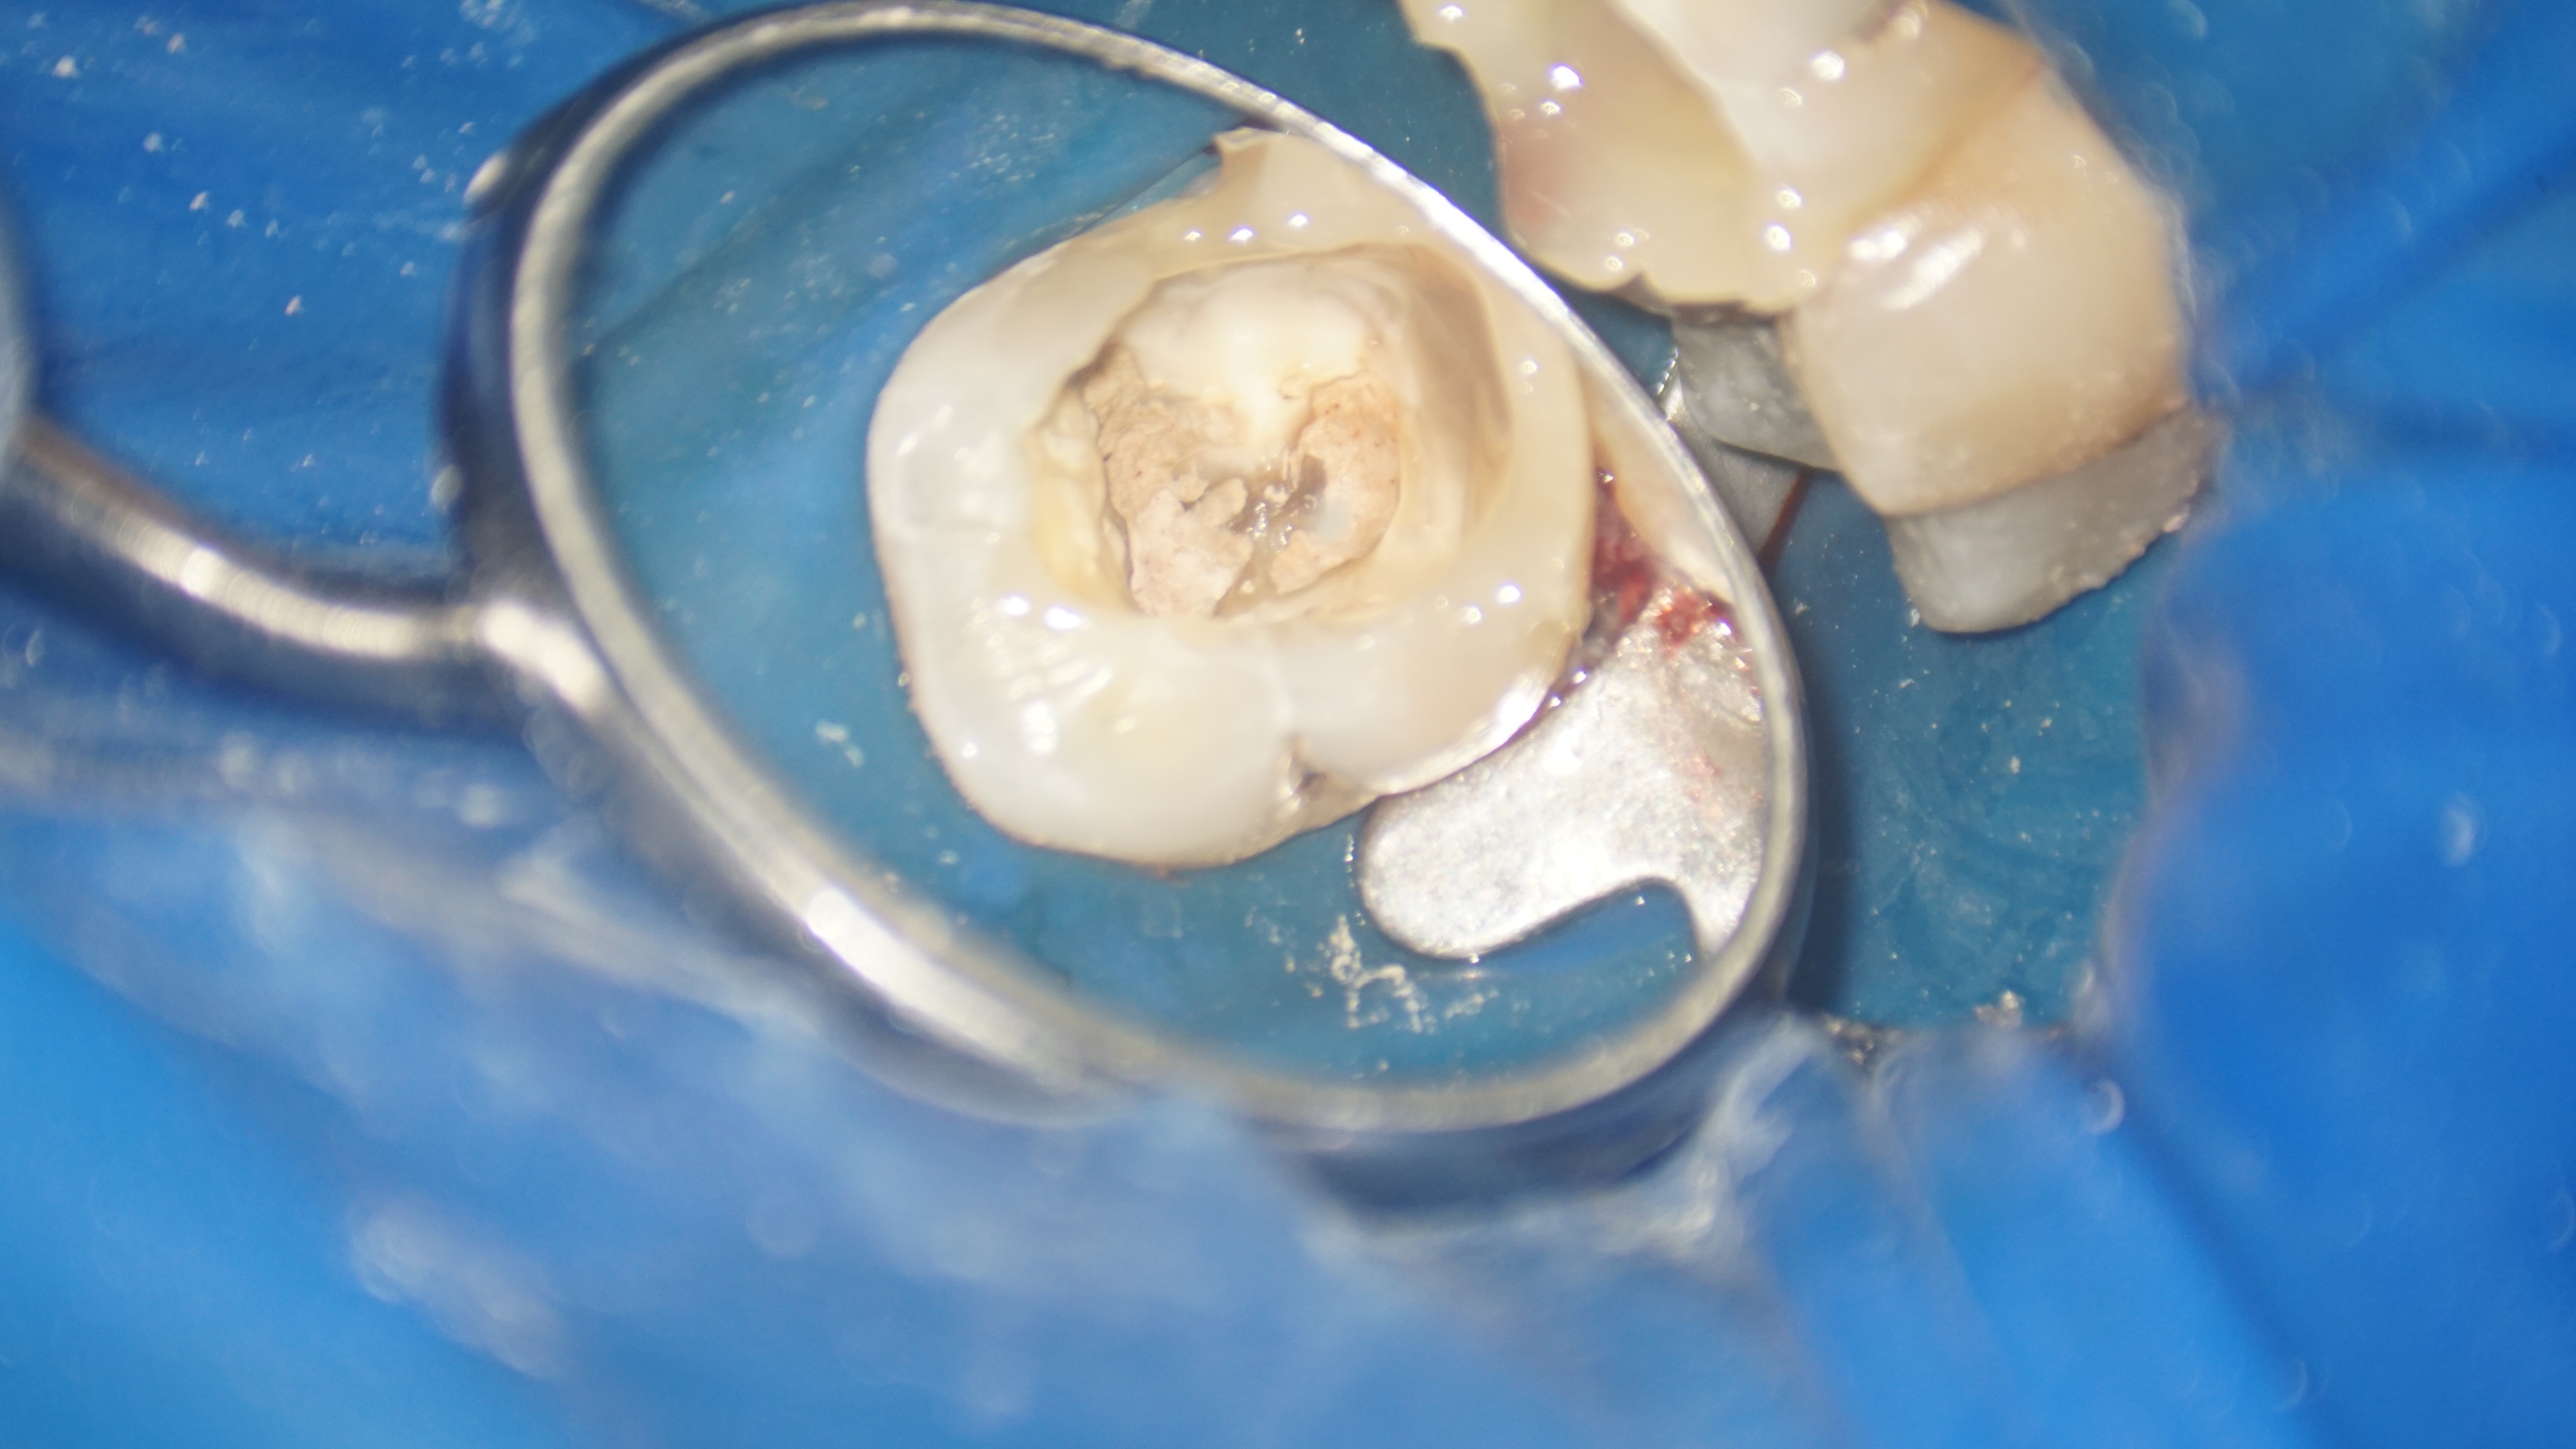

Astfel, s-a decis refacerea tratamentului iniţial, fapt ce a implicat instrumentarea canalelor radiculare și curățarea lor adecvată, realizând bypass-ul (ocolirea) fragmentului din rădăcina mezială şi înlăturarea celui din rădăcina distală. După finalizarea procedurilor, pacientul a raportat dispariția simptomatologiei și ameliorarea disconfortului la masticatie.

În concluzie, cazul a fost abordat cu succes prin efectuarea unui tratament endodontic și prin managementul al fragmentelor de ace ce împiedicau instrumentarea adecvată a spaţiului endodontic. Aceste proceduri au avut ca rezultat vindecarea patologiei și ameliorarea simptomatologiei, restabilind sănătatea și funcționalitatea dintelui.